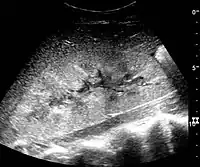

In medical imaging, the acute changes in the kidney are often examined with renal ultrasonography as the first-line modality, where CT scan and magnetic resonance imaging (MRI) are used for the follow-up examinations and when US fails to demonstrate abnormalities. In evaluation of the acute changes in the kidney, the echogenicity of the renal structures, the delineation of the kidney, the renal vascularity, kidney size and focal abnormalities are observed.[16] CT is preferred in renal traumas, but US is used for follow-up, especially in the patients suspected for the formation of urinomas. A CT scan of the abdomen will also demonstrate bladder distension or hydronephrosis.

- Renal ultrasonograph of acute pyelonephritis with increased cortical echogenicity and blurred delineation of the upper pole.[16]